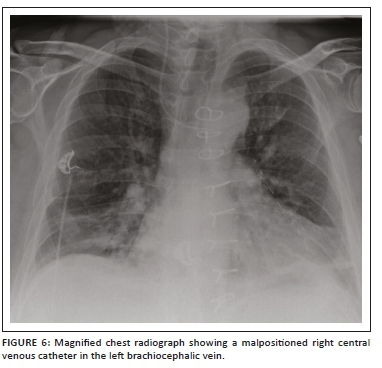

A central venous catheter (CVC), also known as a central venous pressure (CVP) catheter or a central catheter or line, is a catheter (Figure 5a) that provides access for administering drugs or fluids, monitoring central venous or pulmonary artery pressure, monitoring central venous blood oxygen saturation, transvenous cardiac pacing, access for extracorporeal blood products and interventions. These catheters are usually inserted via the subclavian or internal jugular vein and less frequently via the femoral vein. A peripherally inserted central catheter (PICC) is a CVC of smaller calibre (Figure 5b) that is usually inserted via the antecubital vein and remains in place for months.2,11,12 Tunnelled CVCs (Figure 5c) are cuffed catheters that provide long-term intravenous access for a variety of purposes, which include parenteral nutrition, chemotherapy and haemodialysis. The commonest application for this CVC is for haemodialysis in patients with renal failure.13

Most clinicians prefer the CVC tip to be positioned at or just above the cavoatrial junction. As the cavoatrial junction may be difficult to identify on a CXR, the most commonly used and reproducible landmark is two vertebral body levels below the carina. An alternative landmark would be the reflection of the SVC contour with the right heart border and the point where the bronchus intermedius intersects the right heartborder.14 A lower placement is preferred for cannulations introduced from the left side. The various types of CVCs, potential contraindications and complications are shown in Table 112 and Figures 6 and 7.